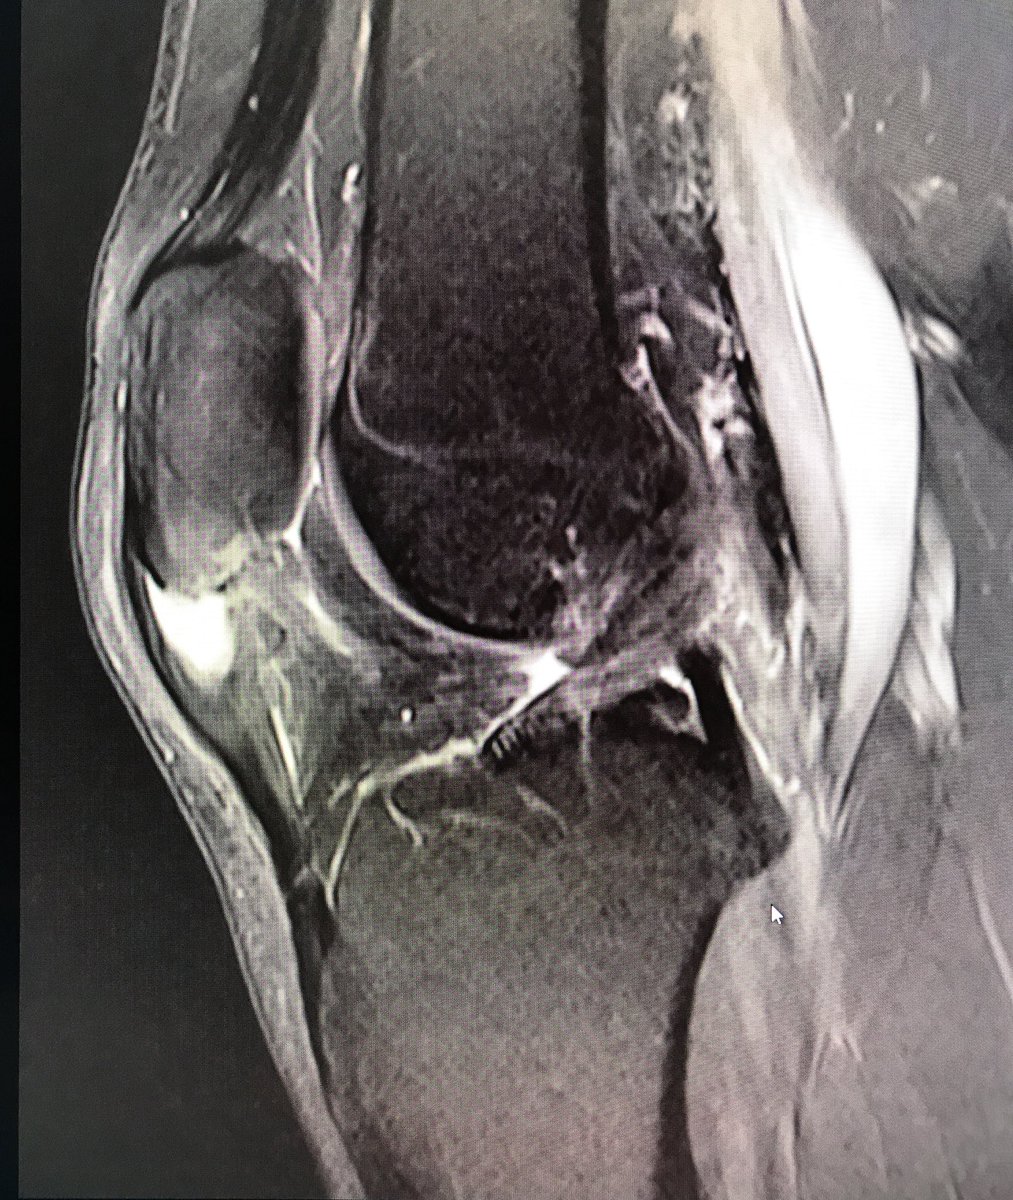

Going a little further back in the archive this week. 'Symptomatic ganglion cyst' at the knee. To read the case history, follow the link. https://www.jospt.org/doi/full/10.2519/jospt.2014.0412 …

#MSKMonday#MSKImaging#MRI#physio#yourJOSPTpic.twitter.com/VNw7p2Xr3X